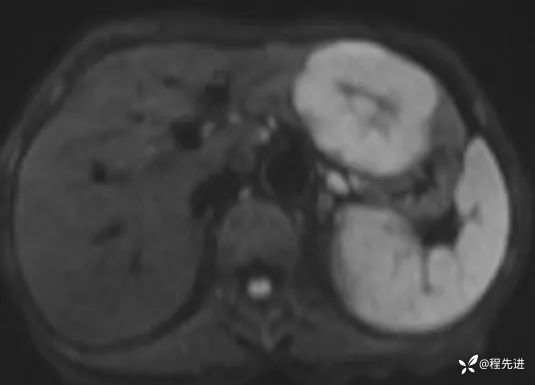

T1同反相位: